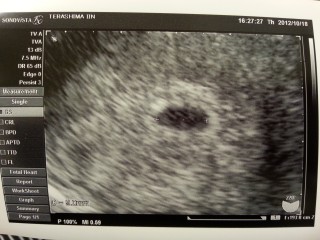

まだ点くらいかもね~と言われながら内診台に乗ったけど、画面にキレイなGSが見えて本当に嬉しかった! 次は2週間後なので、もう毎日そわそわして過ごしてます! 心拍確認が無事に出来ることを祈るばかりです。